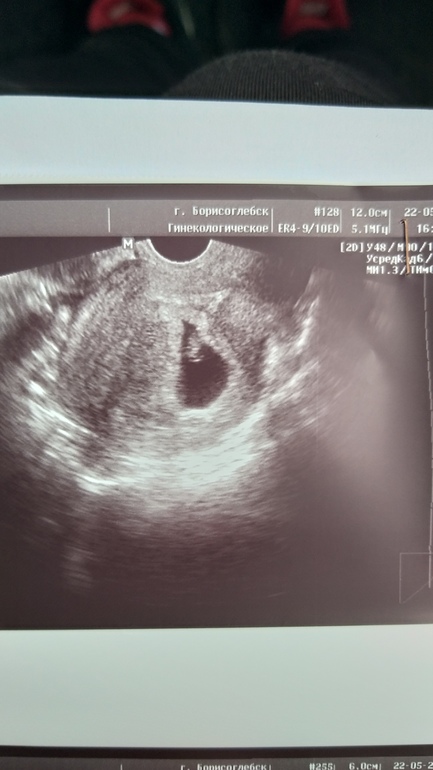

7 нед и 1 день

Девчат, сходила я сегодня на узи. Очень обрадовалась что малышик хорошо, размер малыша 10,4 мм, сердечко 152 уд. Всё по сроку сказали. Но.... девчат меня очень огорчило вот что, может у кого такое было и чем закончилось? Малыш очень очень низко (трое родов у меня преждевременных) ретрохориальная гематома (размер не поняла где смотреть) киста в правом яичнике 60 мм вроде (у меня почти год болел пах тянул, по всем врачам ходила, думали аппендицит, хотели вырезать) локальный гипертонус по всей матке. Небольшая отслойка плаценты сказала. Узистка поставила угрозу прерывания, но сказала в целом все не плохо, не пугала меня. Сказала все у врача узнаешь. К врачу в жк в понедельник. Все выходные ждать, Ааааа!!! Девчата меня больше всего напугала отслойка. Посмотрите пожалуйста бумажки.... я и так в основном лежу и больше 1 кг не поднимаю. Но мне лекарства ничего не выписала узистка, думала скорую вызвать и лечь на сохранение, но что я им скажу, крови нет, ничего особо не болит. Незнаю что делать лежать и ждать понедельника, или вызывать скорую, как думаете? Боюсь сама себе назначать лекарства конечно. После узи немного тянет слева и справа, но мне кажется оно и до этого иногда тянуло, просто я так внимания не обращала.